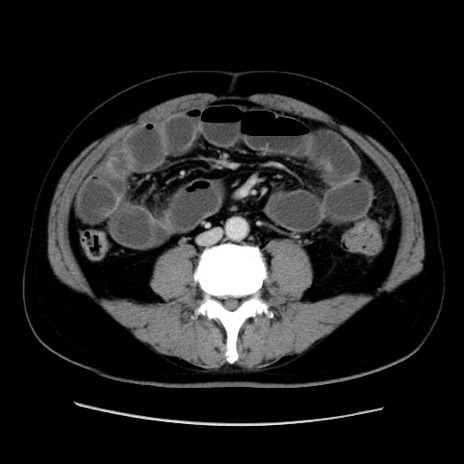

症例16(横断像)

【症例】 70歳代男性

【主訴】 腹痛、嘔吐

【現病歴】 約1ヶ月前より間欠的に腹痛と嘔吐あり、当院消化器内科を受診したところCTで多発する肝臓のLDAを指摘され、精査中であった。以降は消化器症状は安定していたが、2日前より嘔気と腹痛があり、同日より排便・排ガスが消失した。改善認めず、 本日、救急外来を受診した。

【既往歴】 大腸ポリープ切除後。

【身体所見】意識清明・会話良好、BT 36.3℃、BP 127/80mmHg、 P 80bpm、腹部:膨満あり、平坦・軟、上腹部正中および下腹部正中に圧痛あり、反跳痛なし、筋性防御なし。

【データ】WBC 7200、CRP 0.77